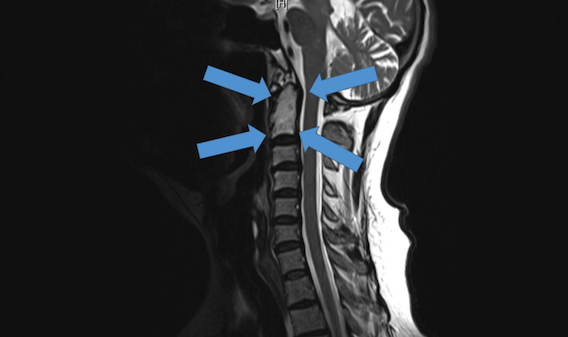

L’homme d’une soixantaine d’années était atteint d’une forme très rare de cancer atteignant la colonne vertébrale, un chordome. Face au risque d’atteintes neurologiques – pouvant aller jusqu’à la tétraplégie – et de métastases vers les poumons le condamnant à une mort certaine, le chirurgien australien a décidé de tenter le remplacement des os par des implants en titane, imprimés par la société locale de produits médicaux Anatomics.

L’intervention représentait un risque important, car les deux vertèbres en question sont difficiles d’accès. « Au sommet du cou, il y a deux vertèbres très spéciales qui sont impliquées dans la flexion et la rotation de la tête », a expliqué le Dr Mobbs au site Mashable Australia.

Ralph Mobbs a alors commandé les répliques exactes des os environnants, reproduits à partir de nombreux clichés radio. Une fois modélisés en 3D, imprimés et assemblés, le chirurgien a pu s’exercer à la procédure avant même d’opérer le patient.